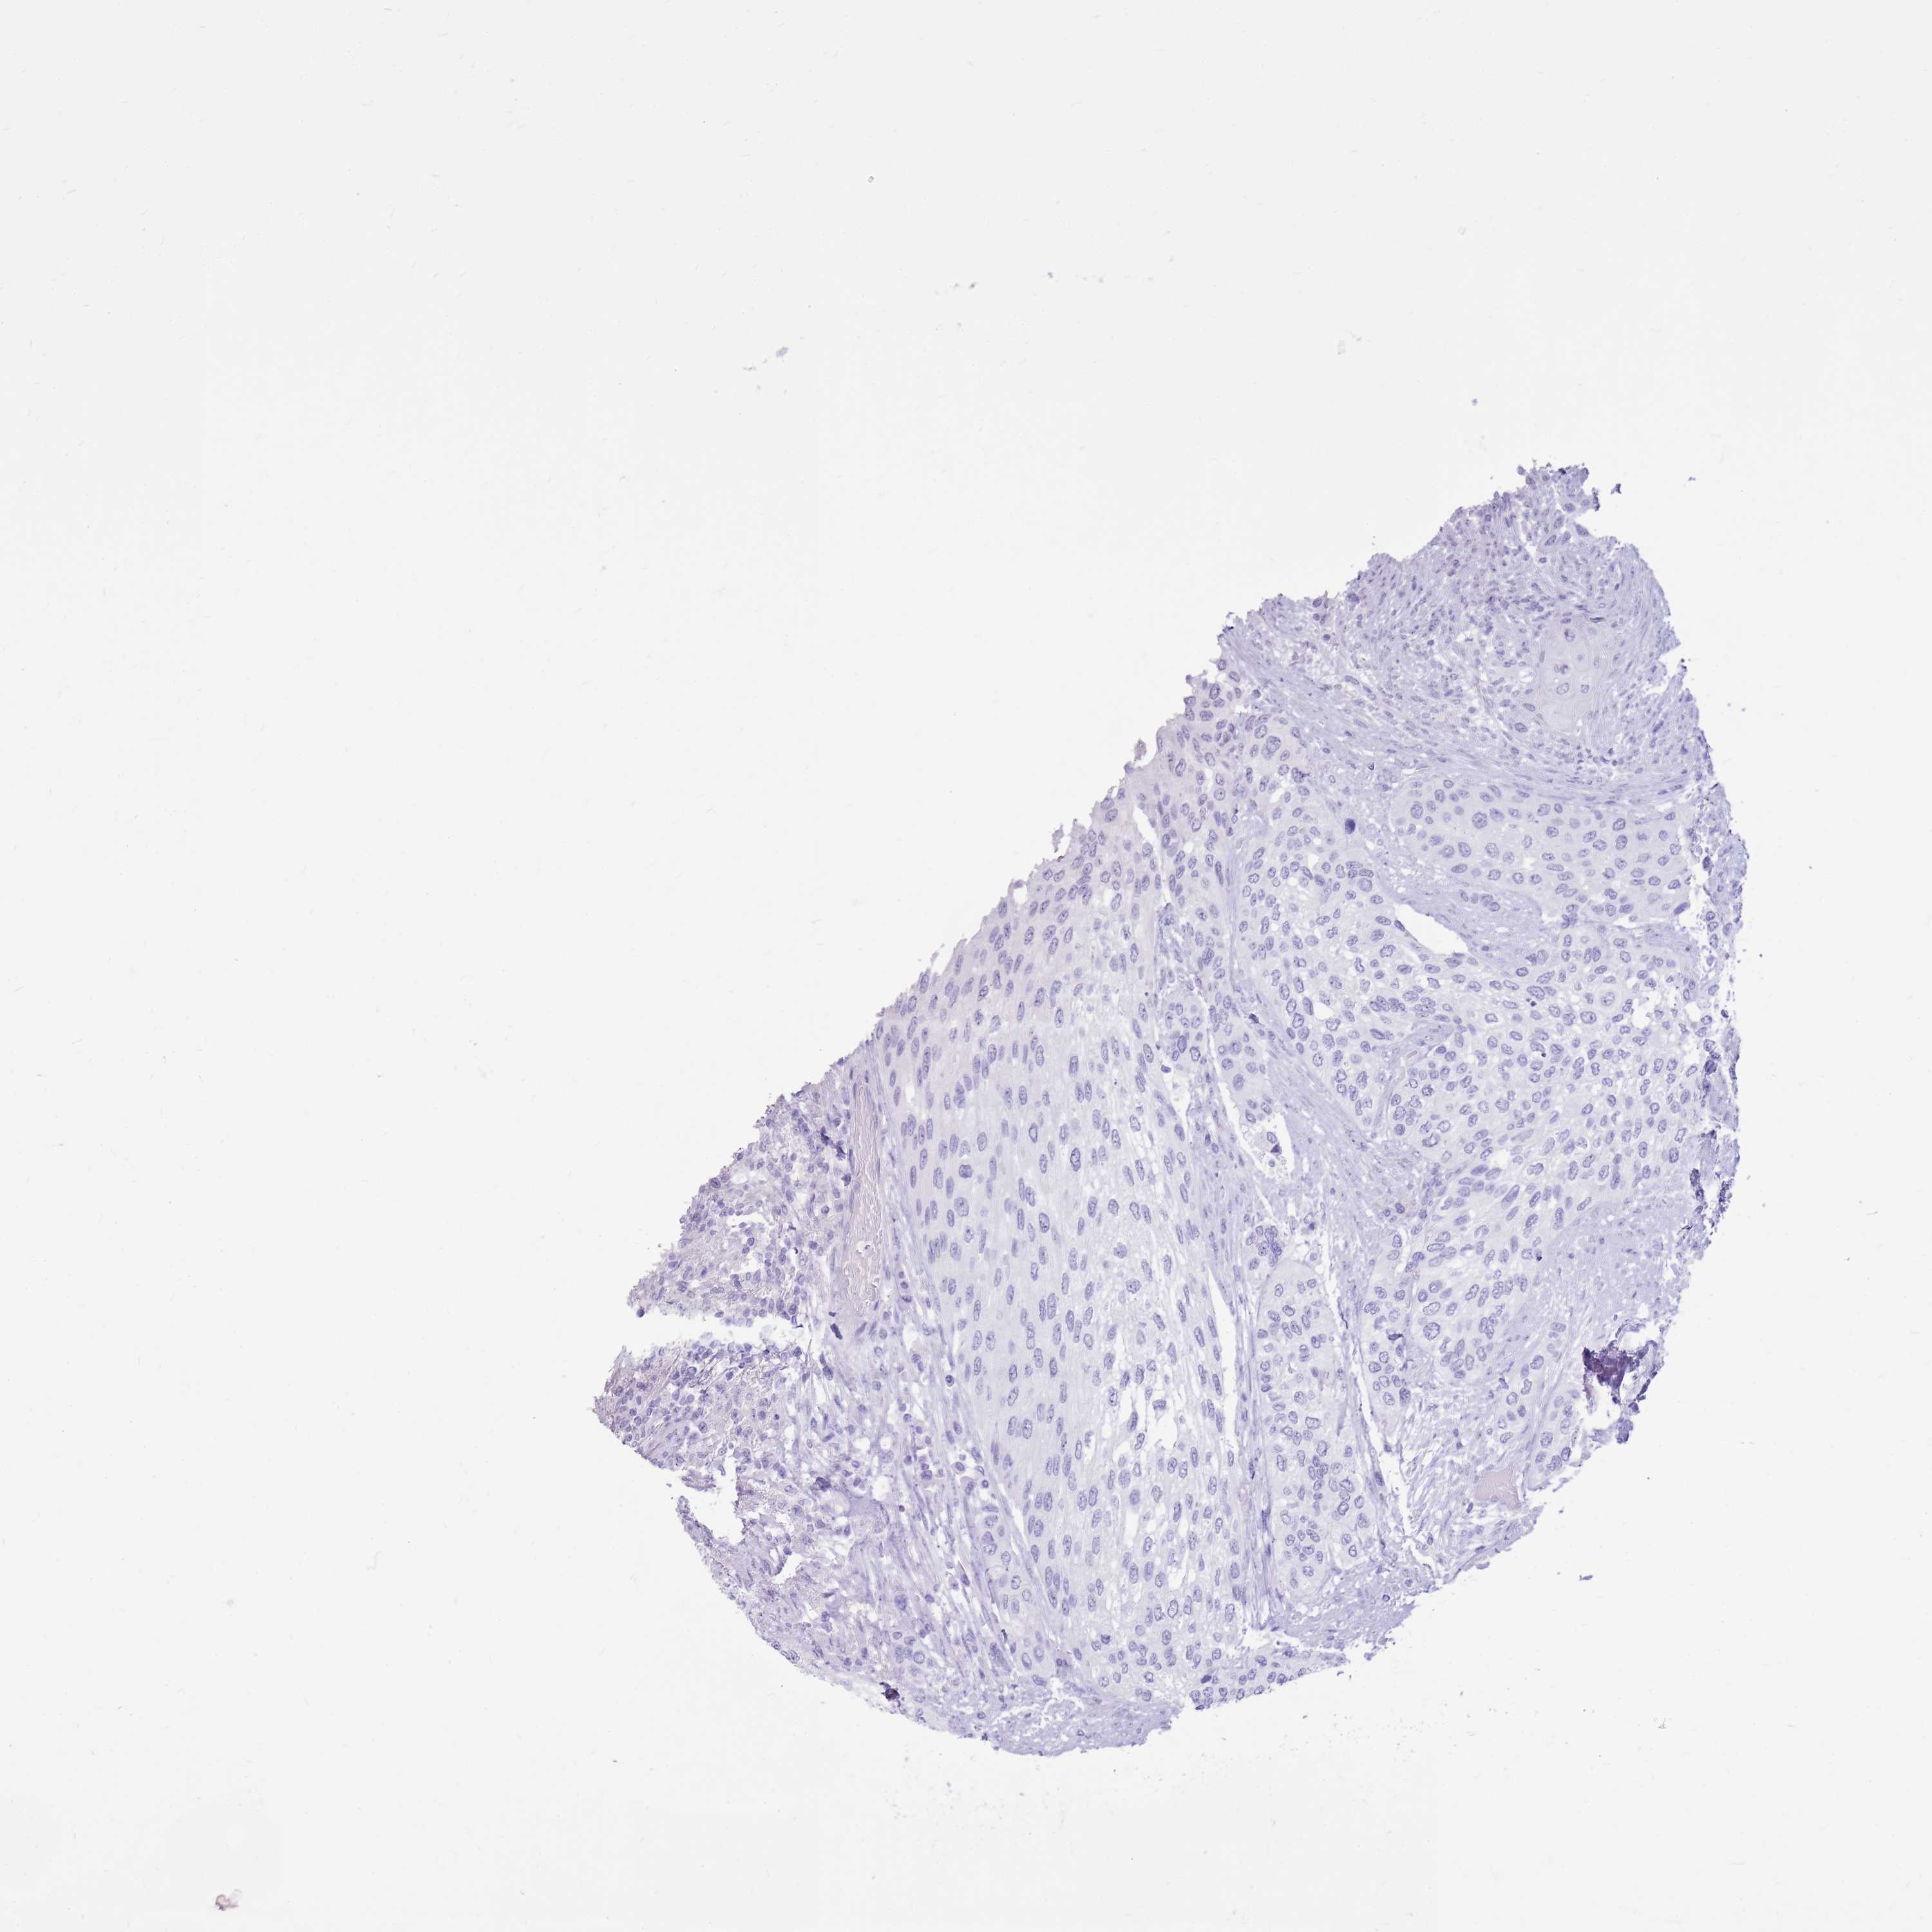

UROTHELIAL CANCER - Protein expressioni

A mouse-over function shows sample information and annotation data. Click on an image to view it in a full screen mode. Samples can be filtered based on level of antibody staining by selecting one or several of the following categories: high, medium, low and not detected. The assay and annotation is described here.

Note that samples used for immunohistochemistry by the Human Protein Atlas do not correspond to samples in the TCGA dataset.

Antibody stainingi

Antibody staining in the annotated cell types in the current human tissue is reported as not detected, low, medium, or high, based on conventional immunohistochemistry profiling in selected tissues. This score is based on the combination of the staining intensity and fraction of stained cells.

Each image is clickable and will lead to virtual microscopy that enables deeper exploration of all samples and also displays staining intensity scores, fraction scores and subcellular localization as well as patient and tissue information for each sample.

Antibody HPA024748

Antibody CAB025545

Antibody CAB047309

Urothelial carcinoma, Low grade

Urothelial carcinoma, High grade

Urothelial carcinoma, NOS